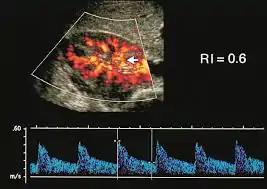

Индекс резистентности (ИР; англ. RI, resistance/resistive index или индекс Пурсело англ. Pourcelot Resistive Index) — отражает разницу между фазами сердечного цикла (систолой и диастолой). Чем выше индекс, тем больше разница. Используется для оценки сосудистой гемодинамики.

Нормальное значение индекса резистентности для почечных артерий для взрослого 0.6-0.7 с верхним пределом нормы. У детей индекс резистентности обычно превышает 0,7 от 12 месяцев до года и может оставаться выше 0,7 от 1 года до 4 лет.

Используется при ультразвуковом исследовании пупочной артерии при плацентарной недостаточности. ИР не должен превышать 0,60 в 30 недель беременности. ИР также широко используется для мониторинга состояния почек, особенно после трансплантации почки.